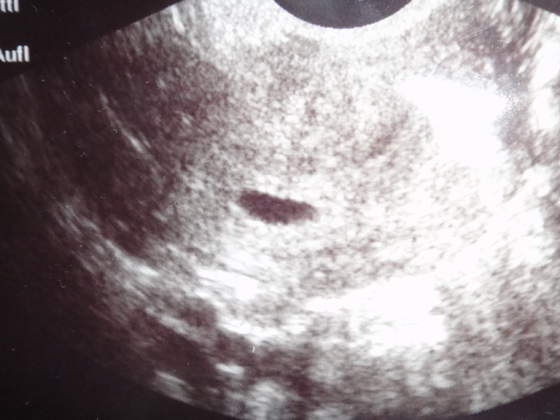

o znalazlam cos podobnego, tzn moj pecherzyk jest mniejszy ale cos podobnego w nim siedzi, tu zaznaczyl ktos ze to dziecko, no ja mam nadzieje ze u mnie tez